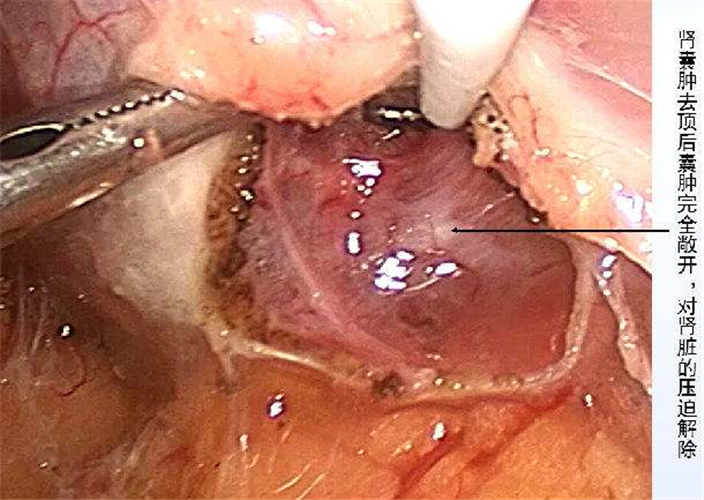

微創治療腎囊腫

腎囊腫手術解說

A:對於5-6cm的腎囊腫,一般需要手術治療。對於腎囊腫,如果直徑在4cm以上,通常建議患者採用手術干預。常用的手術方式有兩種,如下:一、腹腔鏡腎囊腫去頂術,這種手術屬於微創手術,但是需要在全麻下進行,通過腹腔鏡找到腎囊腫,將腎囊腫的囊腫壁頂……